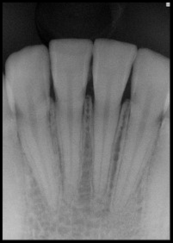

Radiographs